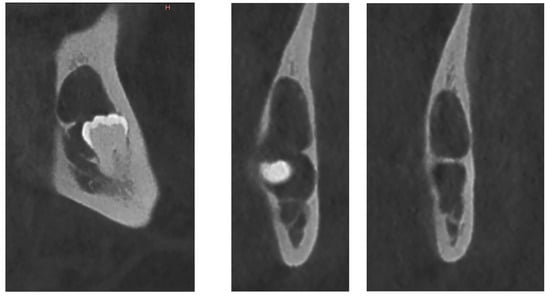

Figure 2.

CBCT X-ray of case #1.

There was also no periosteal reaction, pathological fracture, evident signs of sequestration or sclerosis of the surrounding bone, nor infiltration of the perimandibular soft tissues. Tooth #38 had two roots, and the mesial root came into contact with the lingual wall of the IAC. The radiological appearance evoked a DC. Differential diagnoses included odontogenic keratocyst and unicystic ameloblastoma. The lesion was enucleated in toto together with tooth #38 under local anesthesia. The diagnosis of DC was confirmed by histopathological examination (Figure 3). The patient was followed for four years. At 12 months follow-up, OPG showed satisfactory healing of the enucleation cavity and tooth #37 was still vital (Figure 4). The patient was followed-up for 4 years with no signs of recurrence.